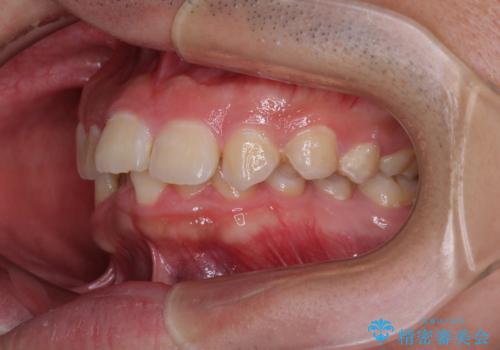

- デコボコと奥歯の咬み合わせのズレを気にして来院された患者様です。

骨格的に、下顎が右側にずれており、左側の咬み合わせに鋏状咬合などのアンバランスが生じている状態でした。

また、上顎前歯に欠損が1本あり、上下ともに前歯部に叢生が認められ、下顎前歯の大半が隠れてしまうほどの過蓋咬合も認められました。

咬合平面を平坦にしながら前歯の咬み合わせを挙上し、デコボコと鋏状咬合も改善していくこととしました。

骨格的な左右差が大きかったため、上下の正中のズレや、左右奥歯の咬み合わせなどは妥協的な仕上がりとなりました。

骨格的なズレに対応するにはワイヤー矯正が至適であり、マウスピース矯正は選択しないようにお話をしました。